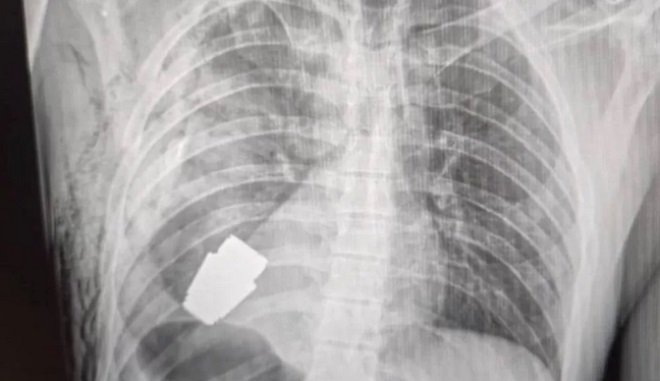

Η είδηση έγινε γνωστή μέσω ανάρτησης στη σελίδα της ιατρικής υπηρεσίας των ενόπλων δυνάμεων της Ουκρανίας στο Facebook, που δείχνει την ακτινογραφία με τη χειροβομβίδα καρφωμένη στο στήθος του στρατιώτη.

Πρόσθεσε ότι η συσκευή ήταν μια χειροβομβίδα VOG - ένα κομμάτι πυρομαχικών μήκους 4 εκατοστών που εκτοξεύεται από έναν εκτοξευτήρα χειροβομβίδων και μπορεί να φτάσει περίπου 400 μέτρα μακριά και είναι σχεδιασμένο να εκρήγνυται ακριβώς πάνω από το έδαφος.